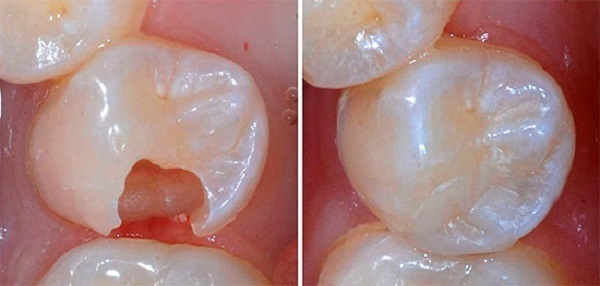

Пломбирование каналов: фото до и после